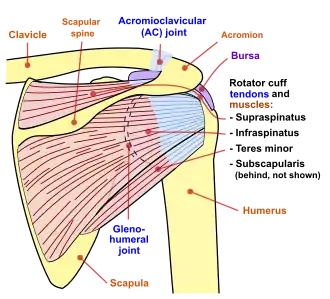

Diagram of the human shoulder joint, back view

Diagram of the human shoulder joint, back view -